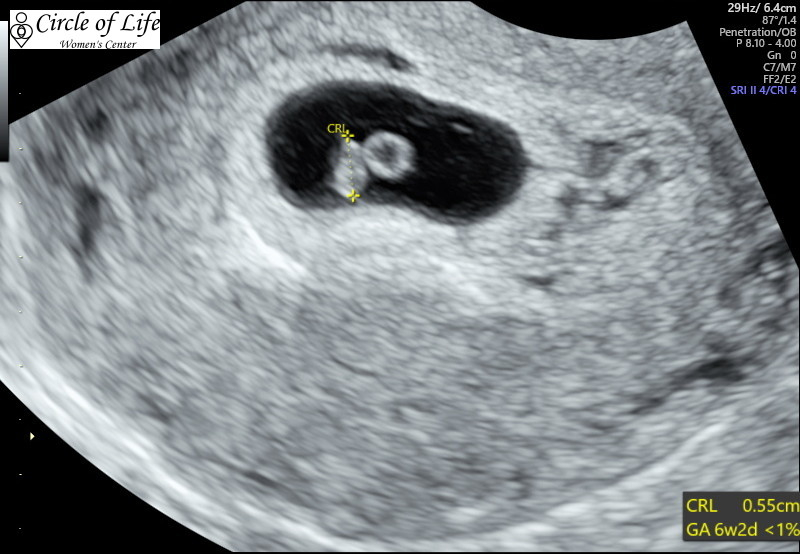

Hi everyone! My EDD is 7/1/2019, so I’m not sure if I’ll be here or in June. Here is our ultrasound photo from 8 weeks (transvaginal) a couple weeks ago. Heartbeat was 172bpm. Baby is the blob on the upper right, facing away.

Here is our ultrasound photo from 8 weeks (transvaginal) a couple weeks ago. Heartbeat was 172bpm. Baby is the blob on the upper right, facing away.